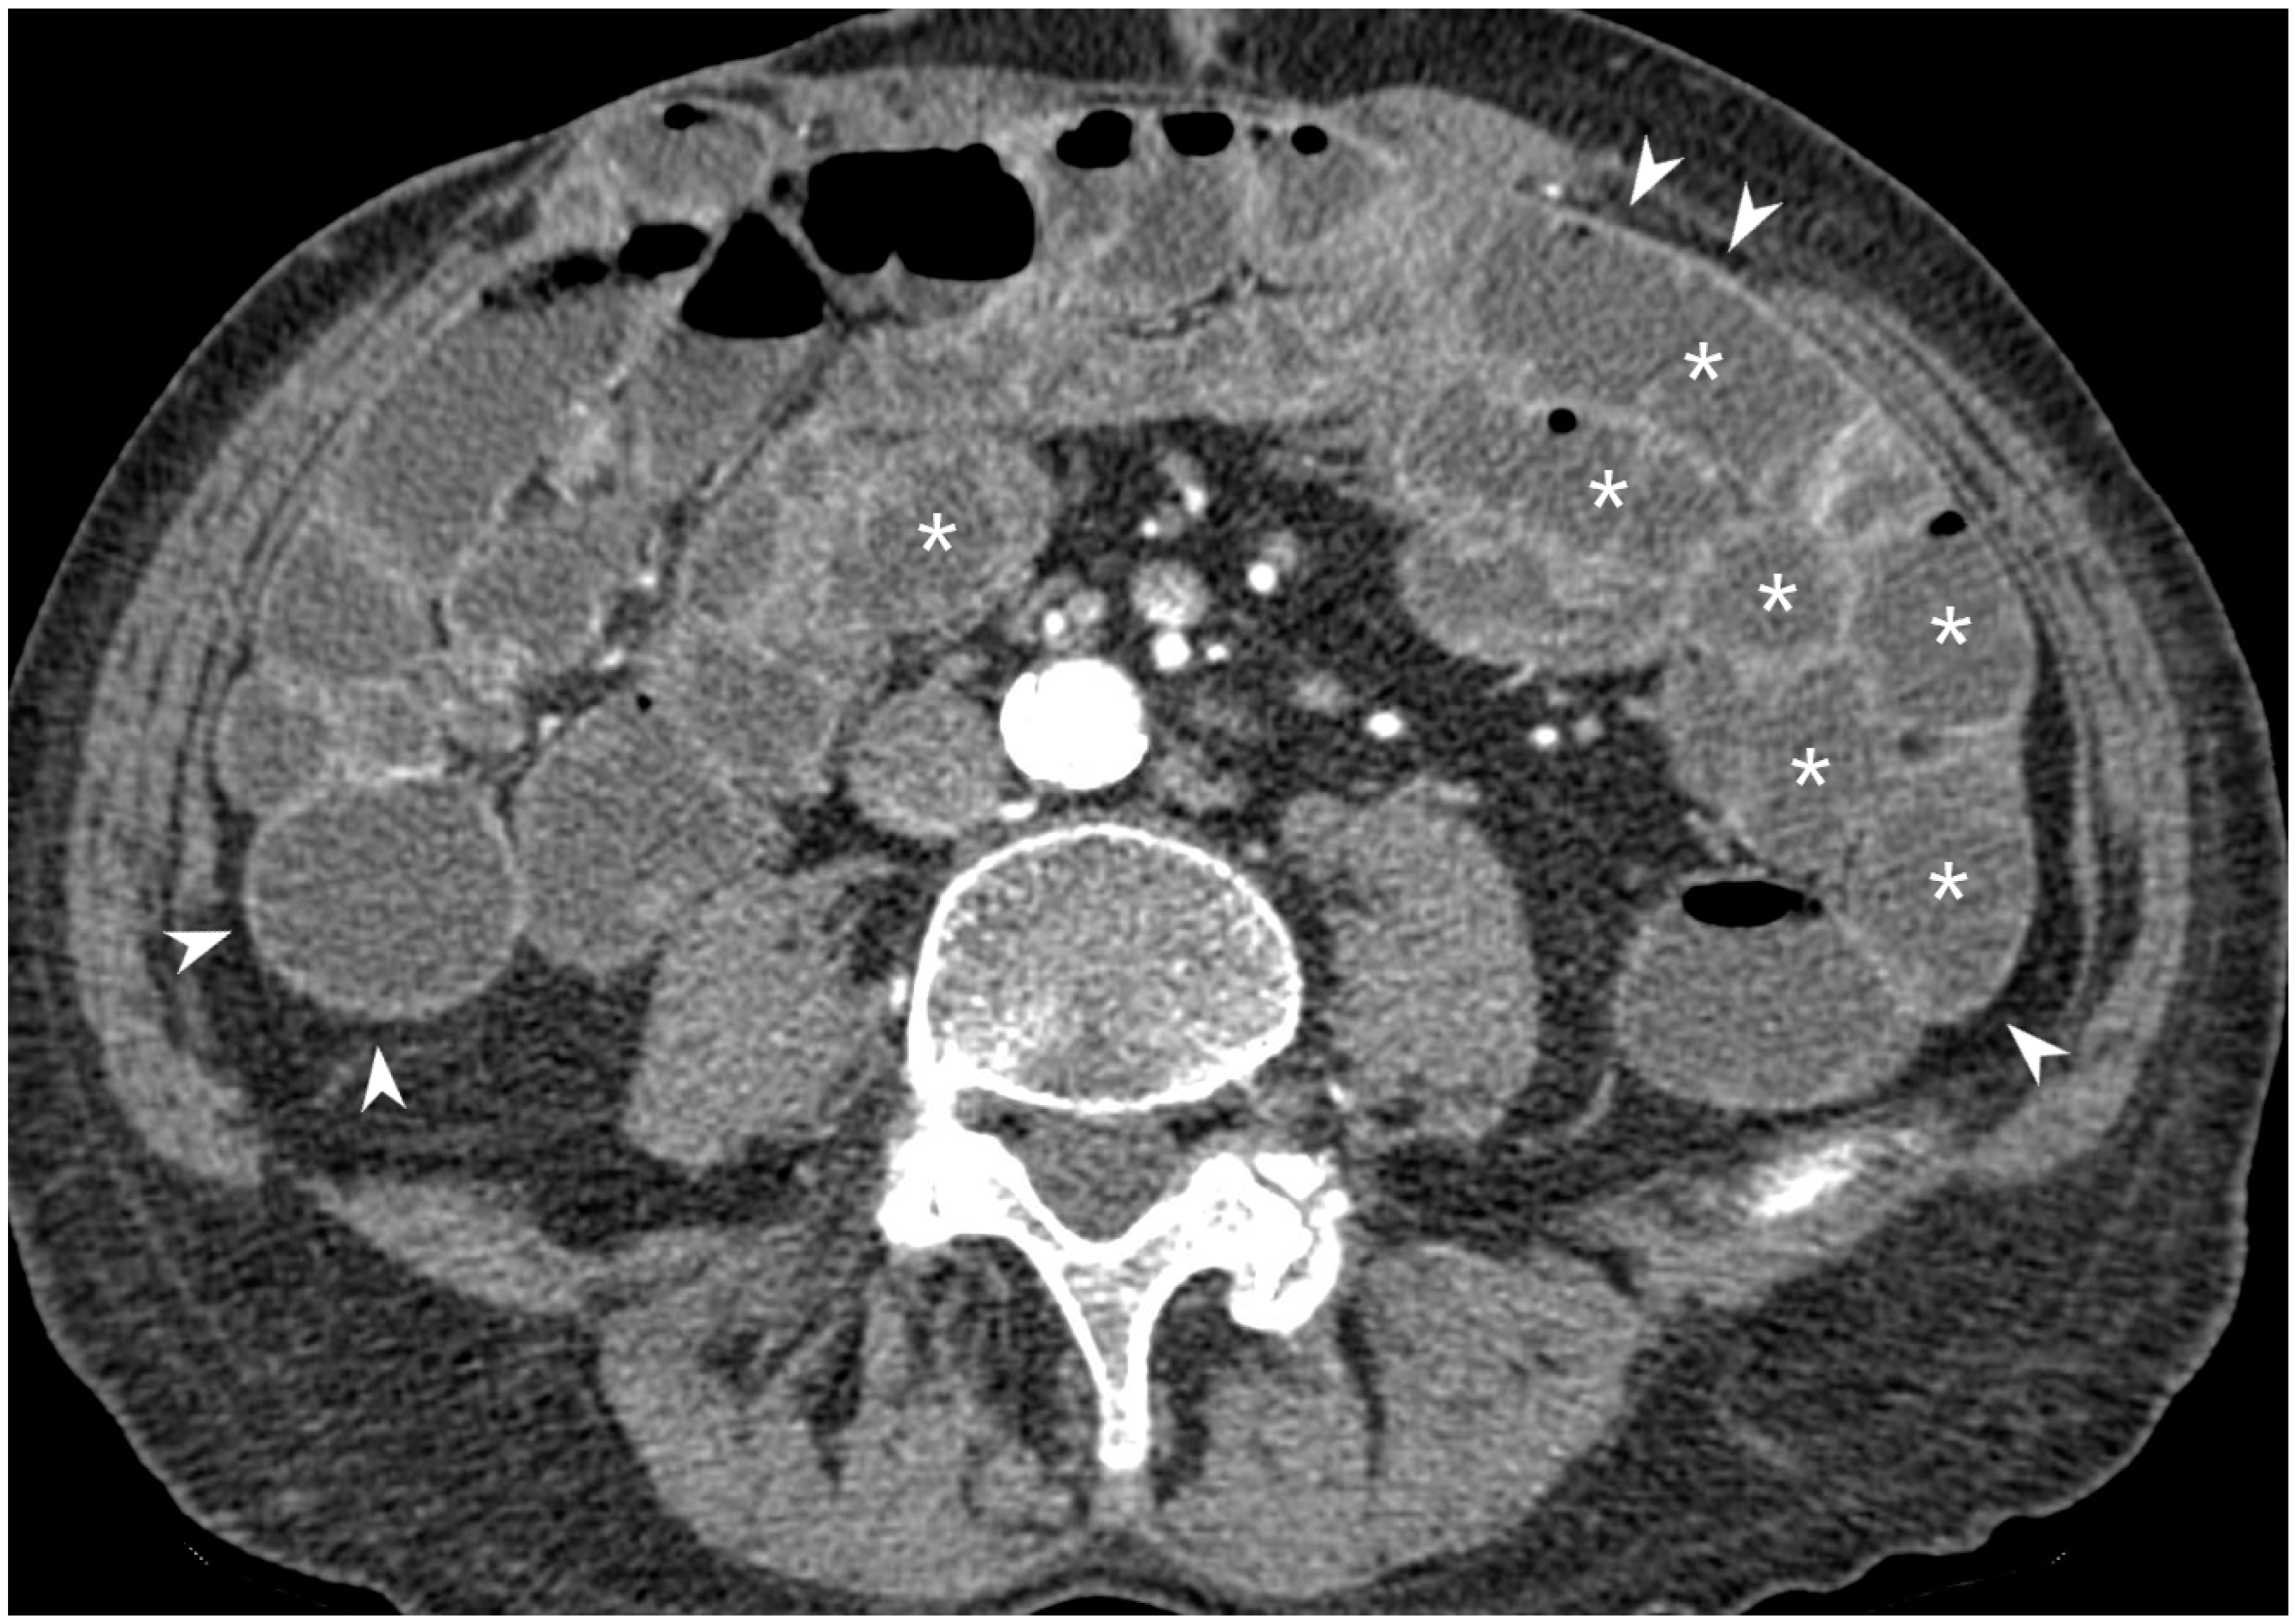

5.3. Fistulising/Perforating Subtype